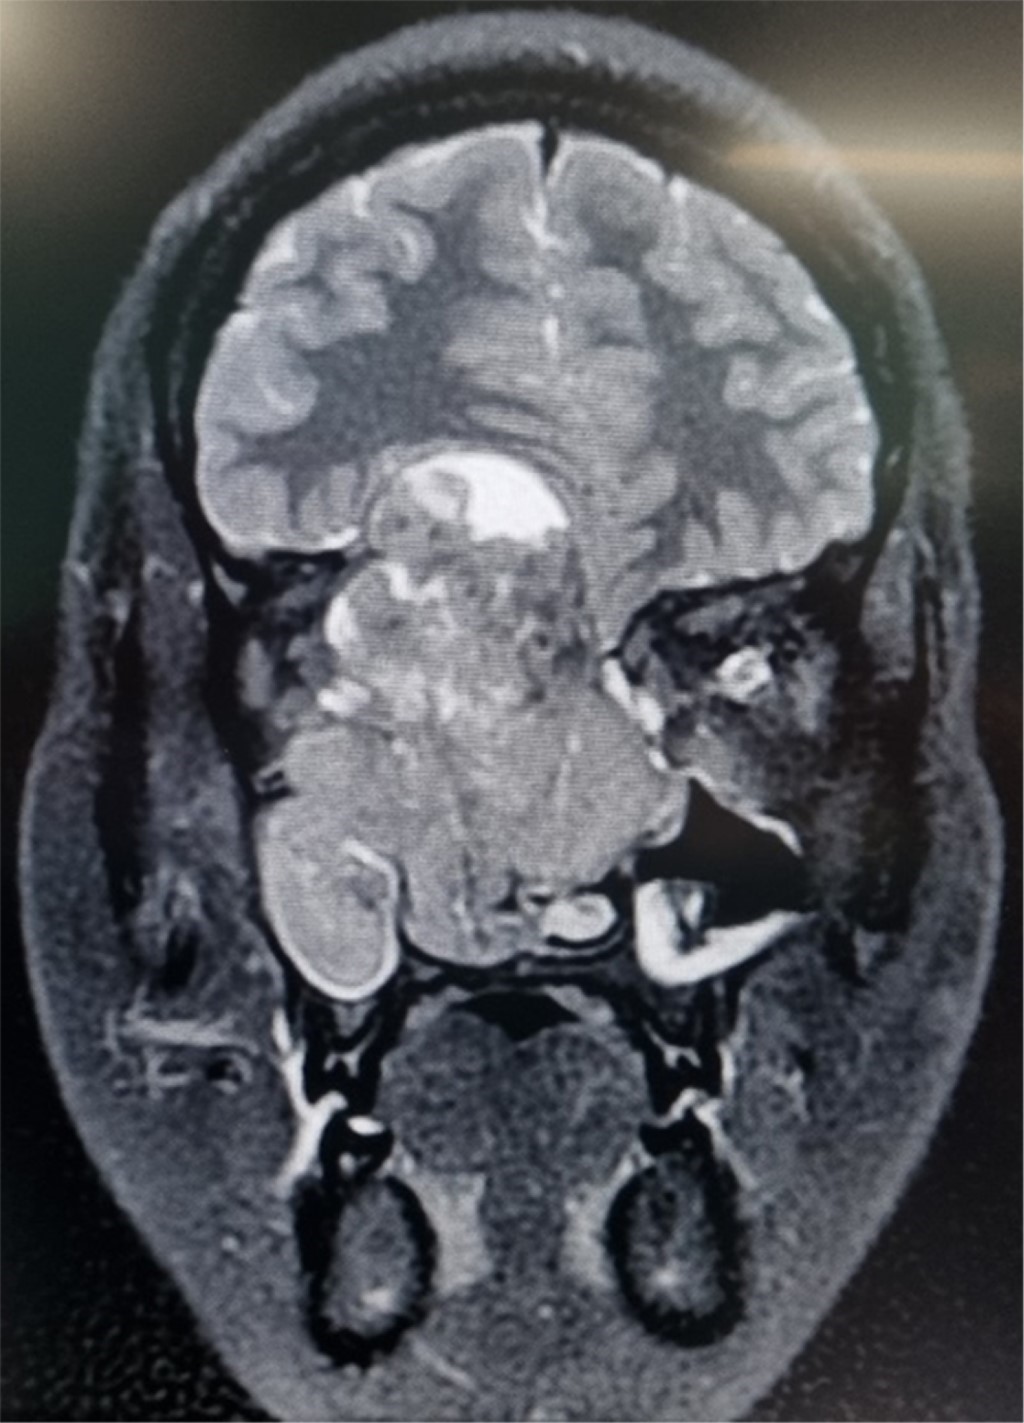

El peso del paciente fue de 67 kg, talla de 1.61 m, índice de masa corporal (IMC) de 25.8 kg/m2, sin predictores de vía aérea difícil. Los estudios paraclínicos de laboratorio se encontraban en parámetros normales. La resonancia magnética evidenció una lesión vascularizada que desplazaba el globo ocular derecho e invadía los senos paranasales (Figura 1). Por este motivo se realizó una toma de biopsia de la lesión. Se diagnosticó un estesioneuroblastoma Kadish C, por lo cual se decidió como plan quirúrgico la embolización y resección de la lesión, y como plan anestésico se decidió otorgar anestesia total intravenosa de tipo manual con monitorización invasiva. Se catalogó al paciente con un riesgo ASA II, con alto riesgo hemorrágico, alto riesgo quirúrgico y riesgo tromboembólico por Caprini moderado.

Figura 1